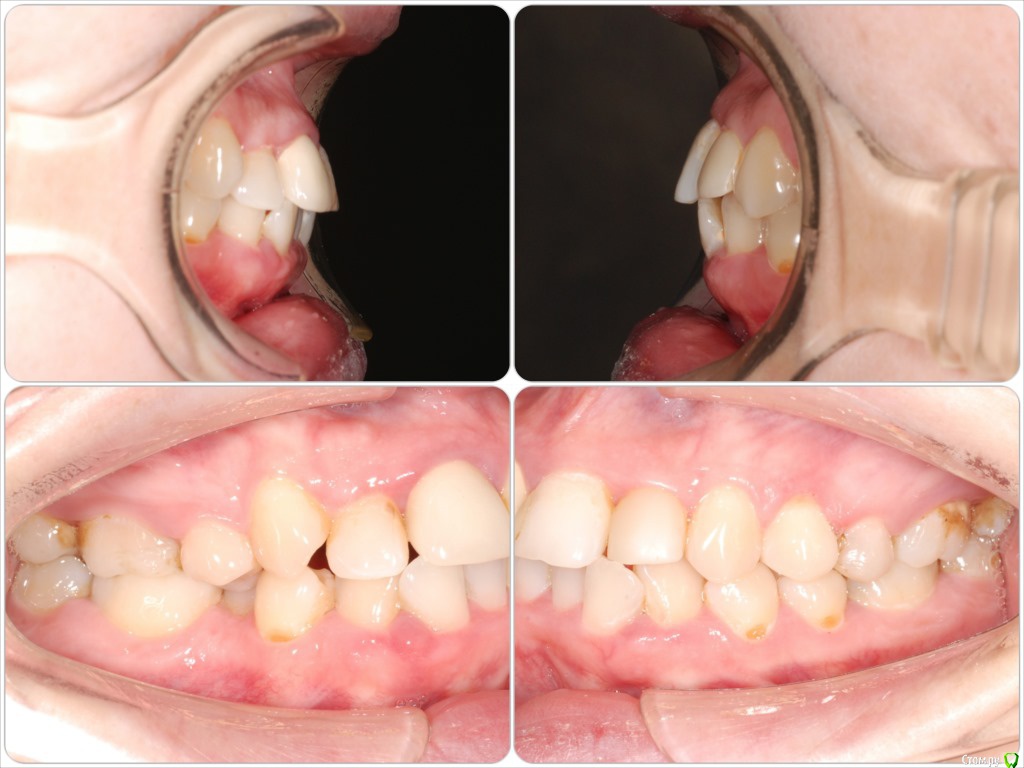

Galaola Опубликовано 28 февраля, 2016 Поделиться Опубликовано 28 февраля, 2016 Добрый день! Мне 36лет. Удалена правая верхняя 4 в детстве. При выборе ортодонта остановилась на варианте без удаления зубов, но с сепарацией зубов НЧ. Через 6 мес лечения ортодонт заявляет об удалении правой нижней 8 как минимум, а лучше всех. Прошу совета и мнения специалистов. Насколько необходимо удаление 8-к? Возможно ли расширить ВЧ и каким образом? Возможно ли подготовить место под имплант отсутствующей 4 или поставить адгезионный мост? Спасибо. Ссылка на комментарий

Brigita Опубликовано 9 марта, 2016 Поделиться Опубликовано 9 марта, 2016 8ки уже не прорежутся, их нужно удалять. Даже прорезанные зубы мудростм все 4 несут жевательную нагрузку около 3%, то есть они абсолютно в Вашем случае ненужные.Имплантация каких зубов планируется? Ссылка на комментарий